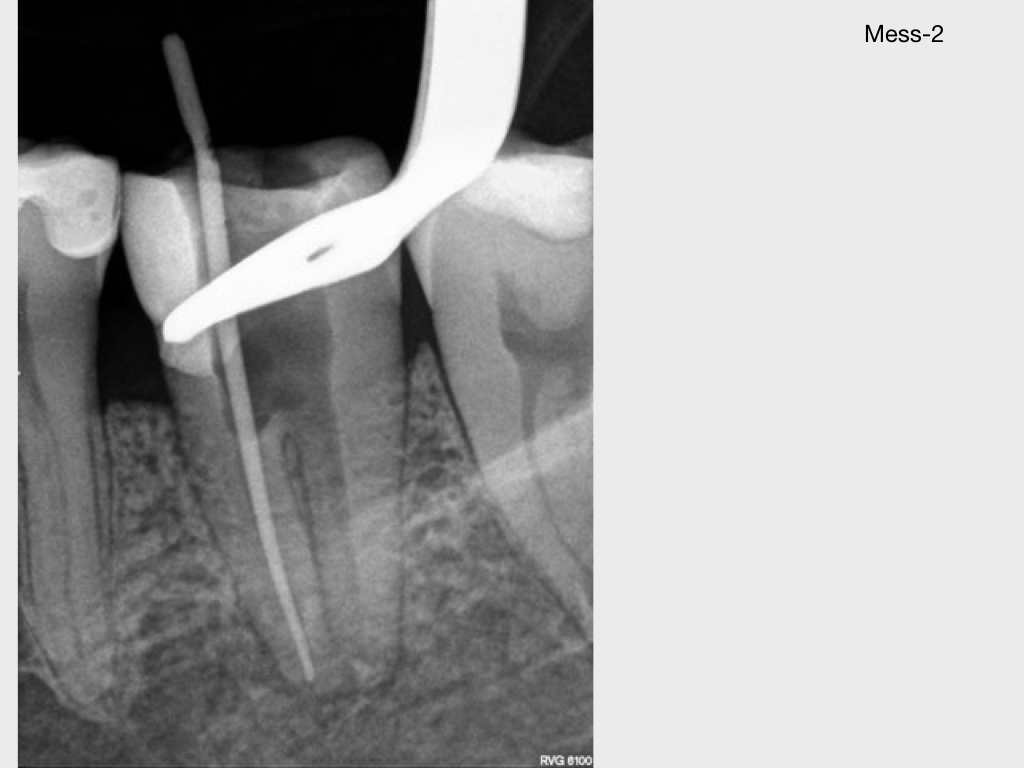

37 mit akuten Beschwerden